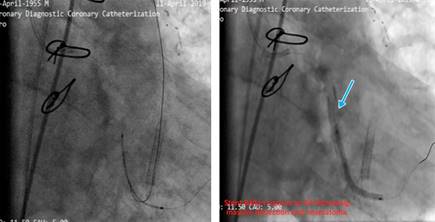

Our aim was to use the SVG as retrograde conduit for CTO PCI. During the procedure stenting was done but the stents balloon ruptured and made a huge dissection which caused a hematoma (Figure 4). As a bailout solution we decided to stent from the ostial LCx (Figure 5). To maintain a sufficient coronary perfusion, we decided to coil occlude due to Thrombolysis in Myocardial Infarction Score (TIMI) flow over 2 in this stenotic and thrombotic SVG so the competitive flow won’t affect the newly opened CTO’s long-term results. While coiling the donor SVG the coil dislodged. During the attempt to snare the dislodged coil with single loop snare, force by this device resulted in fracture in the dislodge coil and made two separated particles. One particle stayed in the descending aorta and the other went to the femoral artery. Both then were snared eventually (Figure 6).

Figure 4: Stenting was done, stent’s balloon ruptured the LCx and created a huge dissection and hematoma.